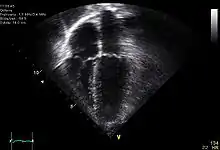

| Diagnostic method | ECG, chest x-ray, bedside echocardiogram |

Diagnosis of traumatic cardiac arrest is initially made with electrocardiogram with EMS or in the emergency department. Clinicians will also order diagnostic testing that may include chest x-ray, bedside ultrasound and echocardiogram, and blood gas levels. A type and cross will be ordered to match the patient to receive blood transfusion if necessary.